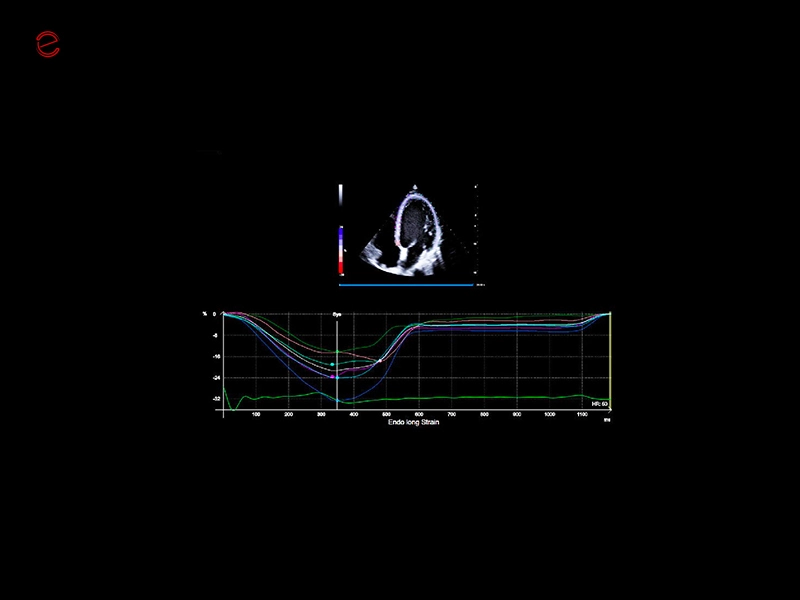

MyLab™X90 - XStrain™ LV Automatic assessment of global longitudinal strain in the left ventricle

MyLab™X90 - XStrain™ LV Automatic assessment of global longitudinal strain in the left ventricle